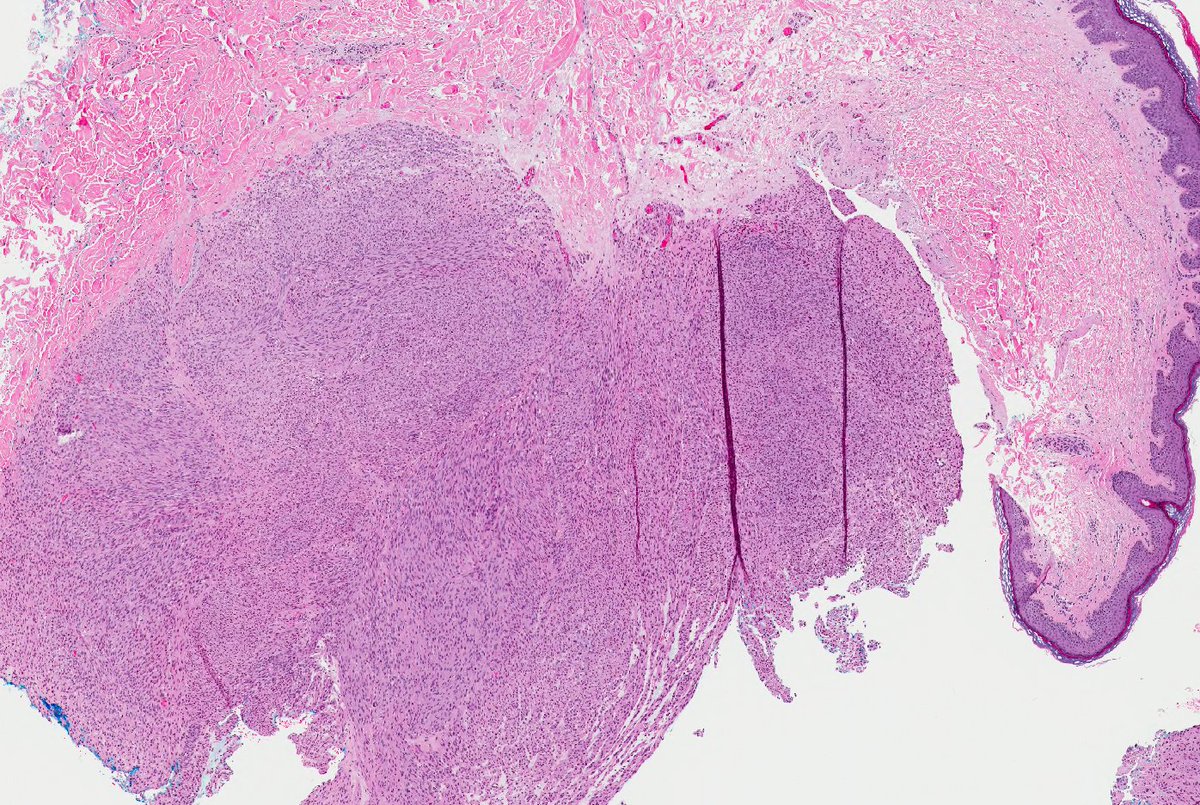

Remember leiomyosarcomas arising from vessels may be aggressive unlike leiomyosarcoma from arrector pili. This LMS arising from vein; note residual vascular wall at periphery. Residual vein top left corner on image 2 & 3. Ref: Italiano A, et al. PubMed PMID: 20167595. #dermpath

SteveBillingsMD's tweet image. Remember leiomyosarcomas arising from vessels may be aggressive unlike leiomyosarcoma from arrector pili. This LMS arising from vein; note residual vascular wall at periphery.  Residual vein top left corner on image 2 & 3. Ref: Italiano A, et al. PubMed PMID: 20167595. #dermpath